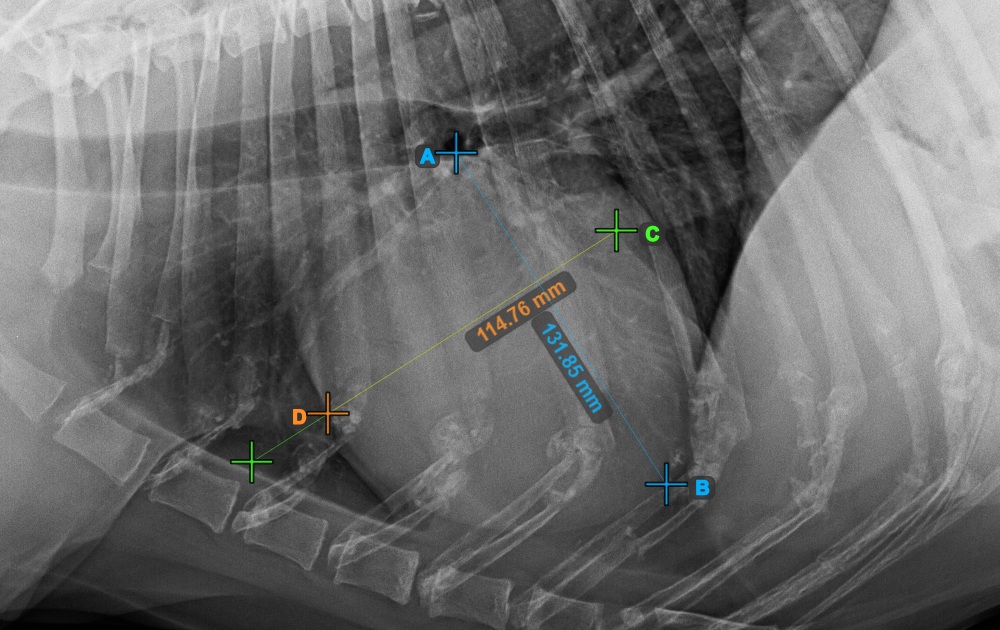

Continue the measurement by marking the widest right (cranial) point of the short axis of the heart.

The image below represents a typical placement of the most cranial point on the short axis of the heart.

Complete the short axis of the heart by marking the widest left (caudal) point.

The image below represents the typical placement of the most caudal point on the short axis of the heart.